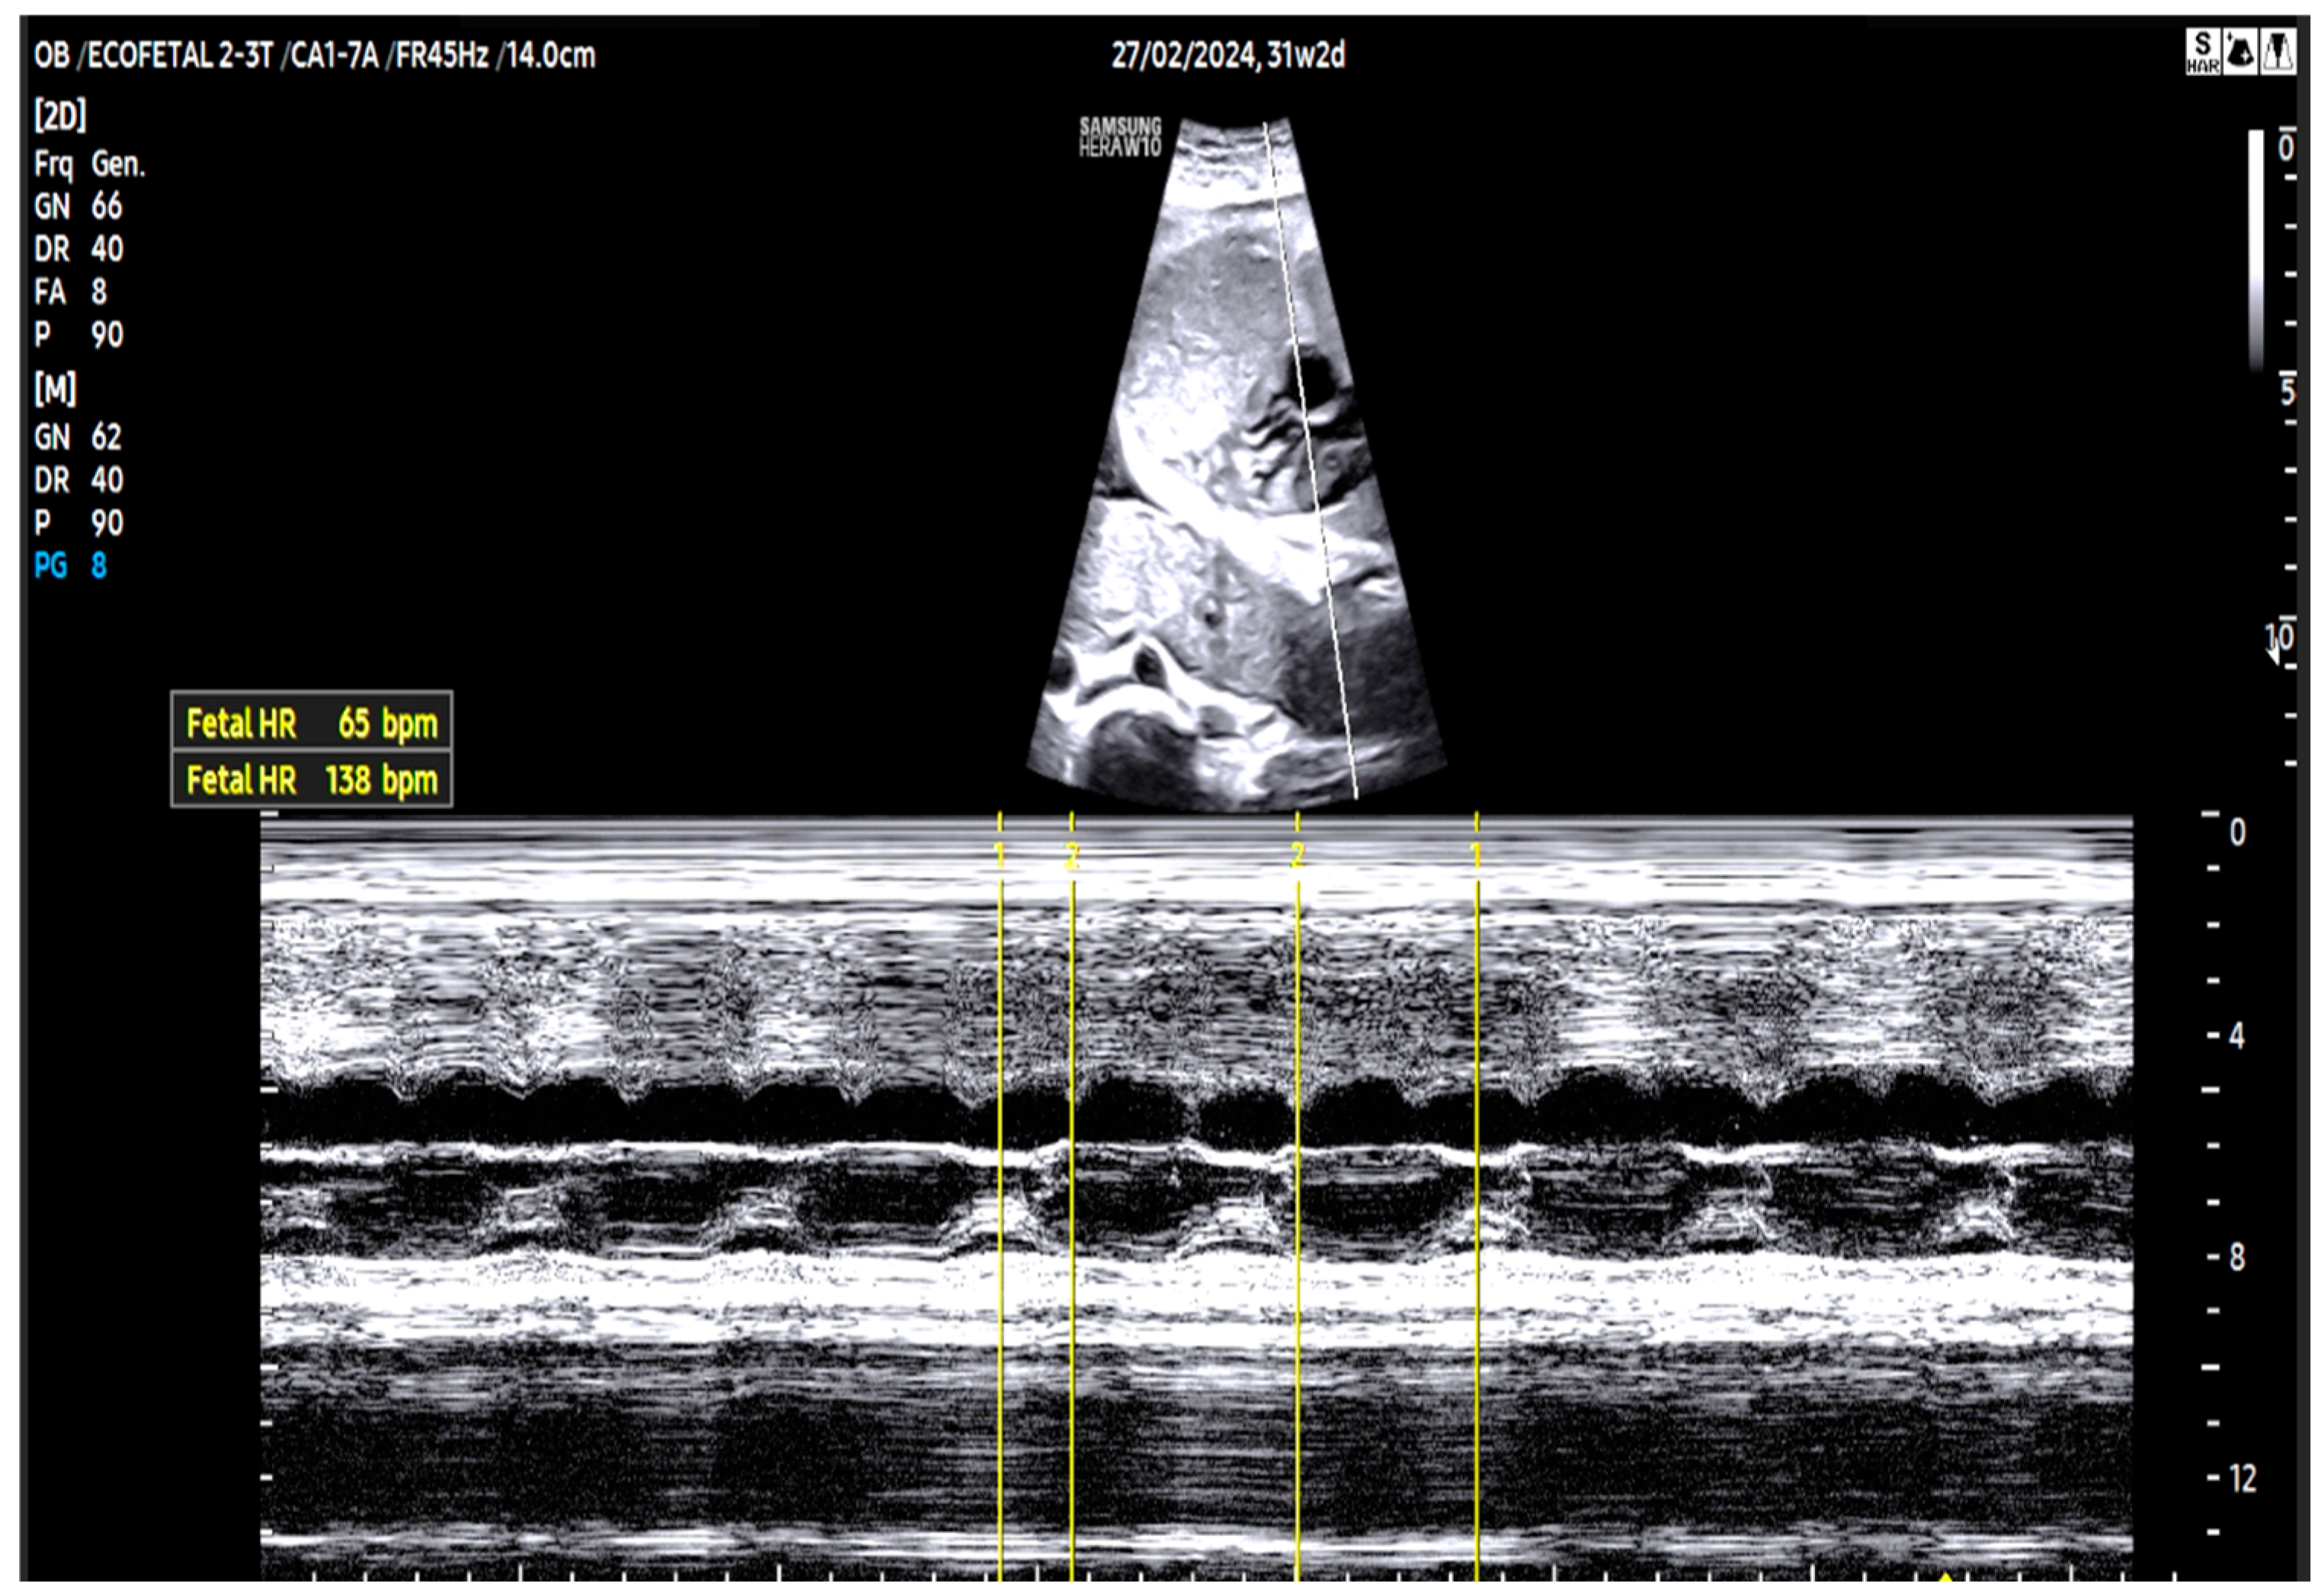

| 26 + 0 | Start of dexamethasone 4 mg/day | 60 | SF increased from 34% to 47%, but qualitative contractility decreased | Mild edema; no beta- agonists used |

| 28 + 0 | First IVIG cycle (65 g total) | 75 | SF increased to 52%; mild improvement in contractility | Initiated due to signs of fibroelastosis |

| 31 + 2 | Post-IVIG peak response | 70 | SF: 59% (LV), 52% (RV); marked biventricular improvement | Aortic isthmus 3 mm (Z-score –1.65) |

| 33 + 0 | Second IVIG cycle | 68 | Stable function maintained | Repeated full protocol; no complications |

| 36 + 3 | Delivery | 84 | – | Stable neonate; no pacemaker needed |